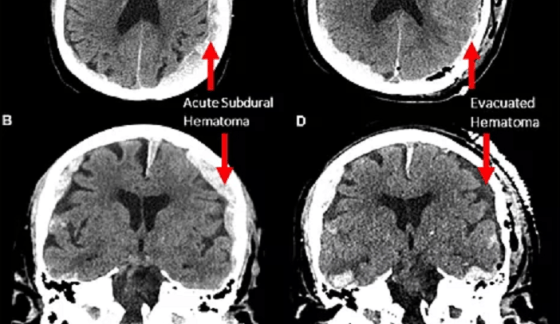

Comprobado: La vida pasa ante nuestros ojos antes de morir

Un «accidente» científico registra la primera ‘grabación’ de un cerebro moribundo. Por Alcides Blanco para Noticias La Insuperable La vida … Más